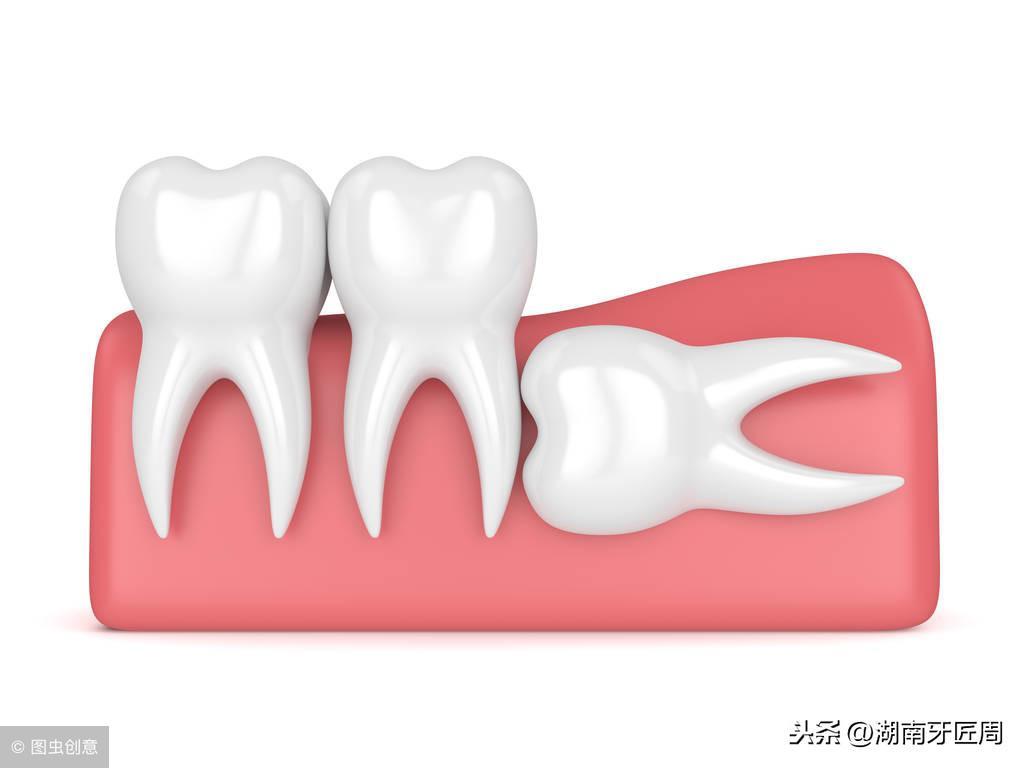

下颌骨结构得不到充分的咀嚼功能锻炼,逐渐退化,牙量大于下颌骨量,这样当第三磨牙长出时就常常位置不够,以致萌出困难,这就形成了“智齿阻生”,智齿阻生是青壮年人的一种常见病。

下颌智齿能够正常萌出并且有正常的咬颌关系者仅仅占很少数,“智齿”萌出时由于没有足够的空间,很容易长歪,例如出现向颊侧或者舌侧倾斜、向前后倾斜等情况。